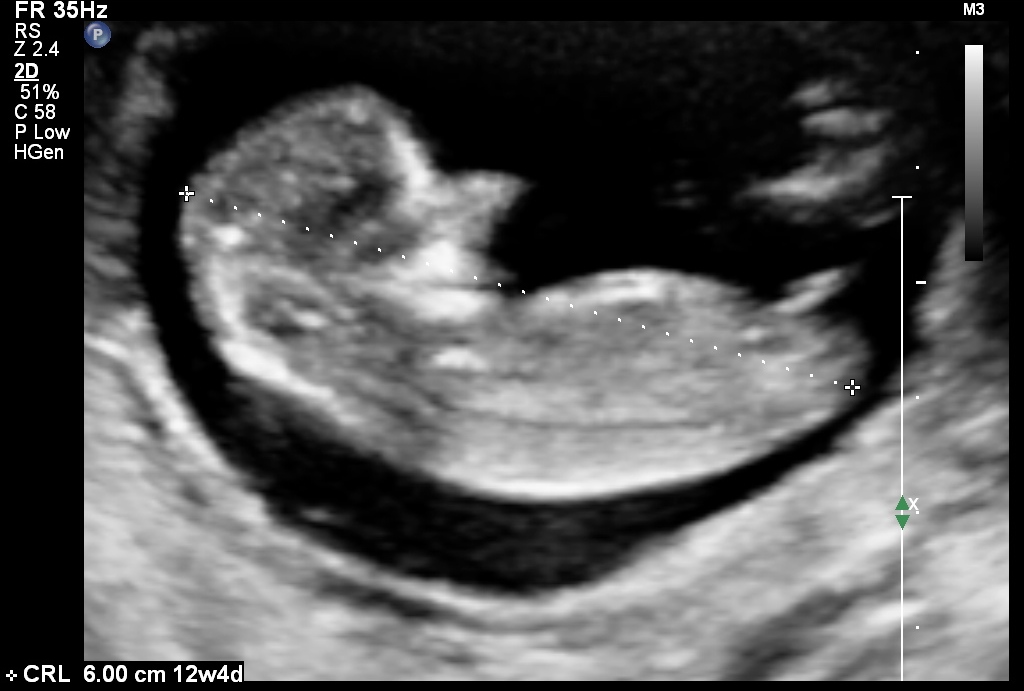

Im posting pics from my NT scan where i was 12 weeks along but baby measured 12w4days.. i have got mostly boy guesses but wud like to see what u all think. Attachment 25368Attachment 25369